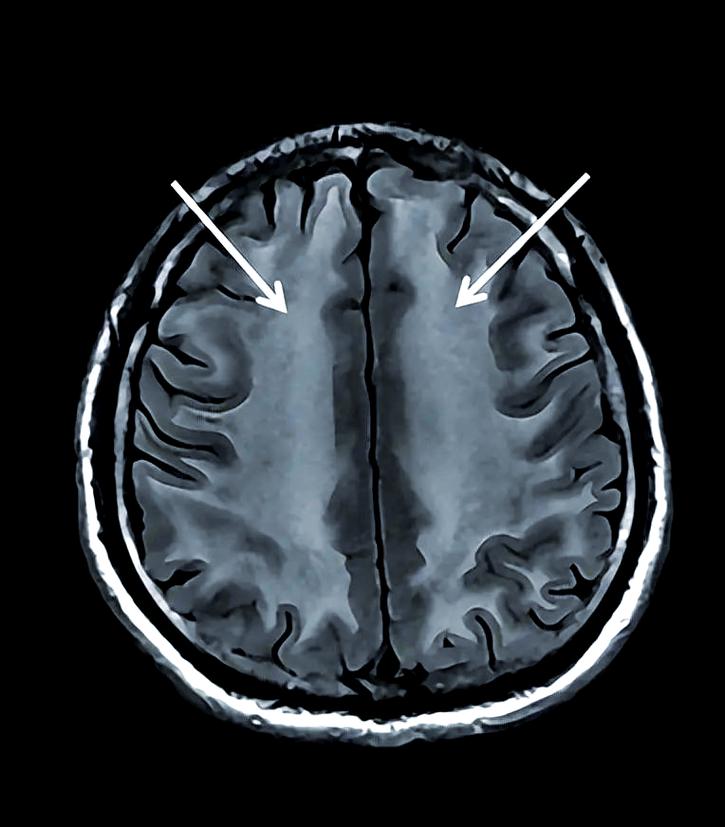

脑白质变性

- “脑白质”是大脑内部神经纤维聚集的区域,负责不同脑区之间的信息传递,它就像连接各个城市的“高速公路网”。

- “变性”指的是这条“高速公路网”的结构和功能出现了问题,变得不光滑、不结实,甚至出现“坑洼”和“断点”。

- 通俗理解:想象一下,原本平坦宽阔的高速公路,因为年久失修、材料劣化或长期受压,路面开始出现裂缝、磨损,甚至局部塌陷,信息传递的速度就会变慢,甚至出错。

- 慢性过程:通常是长期、缓慢发展的过程,在影像学上(如MRI)才能清晰看到。

- 非特异性症状:症状比较隐匿和广泛,不像脑梗那样“一针见血”,常见症状包括:

- 记忆力下降

- 反应变慢

- 注意力不集中

- 情绪不稳、抑郁

- 步态不稳、容易跌倒

- 头晕、头痛